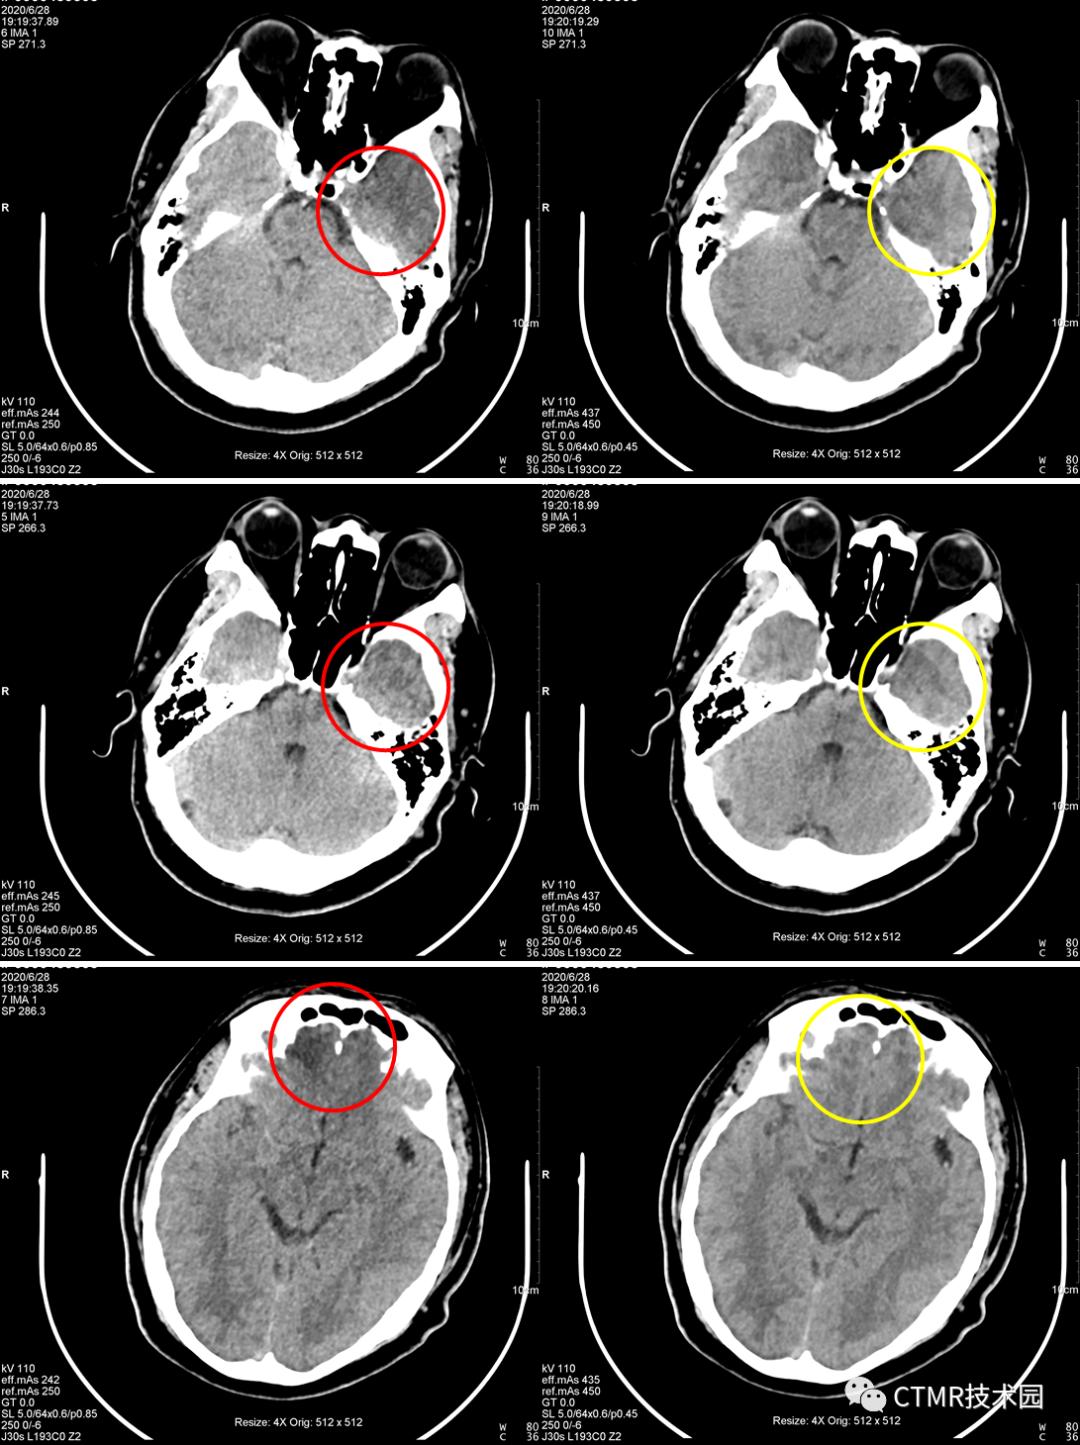

问题1:为什么都是经常出现在右侧呢?因为颅脑大致头足范围都差不多,且都是从头向足螺旋扫描,那么螺旋扫描时可能恰好采集伪影区域层块时,是从头左侧先转的一整圈,那么就导致了右侧不在一个完整的环上,因为转过来时已经跑到下一层块了。其实有时病人以 1.1 螺距扫描是没有伪影的,比如头颅扫描范围有所偏差时,那么上一圈扫描结束位置恰好在前 A 位置,那么伪影这一层块扫描时时恰好左侧与右侧颞部基本都在一整圈范围内。这样的情况也是会出现的,那么此时图像上右侧就不会出现明显的暗区伪影。为了验证如此,我还将扫描顺序更改了下,按足向头扫描(如下图),恰恰暗区伪影经常出现在左侧。当然球管到底是怎么转的,如果能够打开机架外壳,仔细看看就好了。

对比时注意观察图像左下角参数。

问题2:130kV 配合 1.1 螺距可以吗?

不可以。会出现与暗区相反的结论。即在原来右侧(扫描方向头向足)容易出现暗区,那么用 130kV 配合 1.1 螺距会出现在左侧(扫描方向头向足)容易出现亮区。原来右侧暗区的地方反而正常了。那么经过上面讨论可知,要想用 130kV 也得要配合小点的螺距。